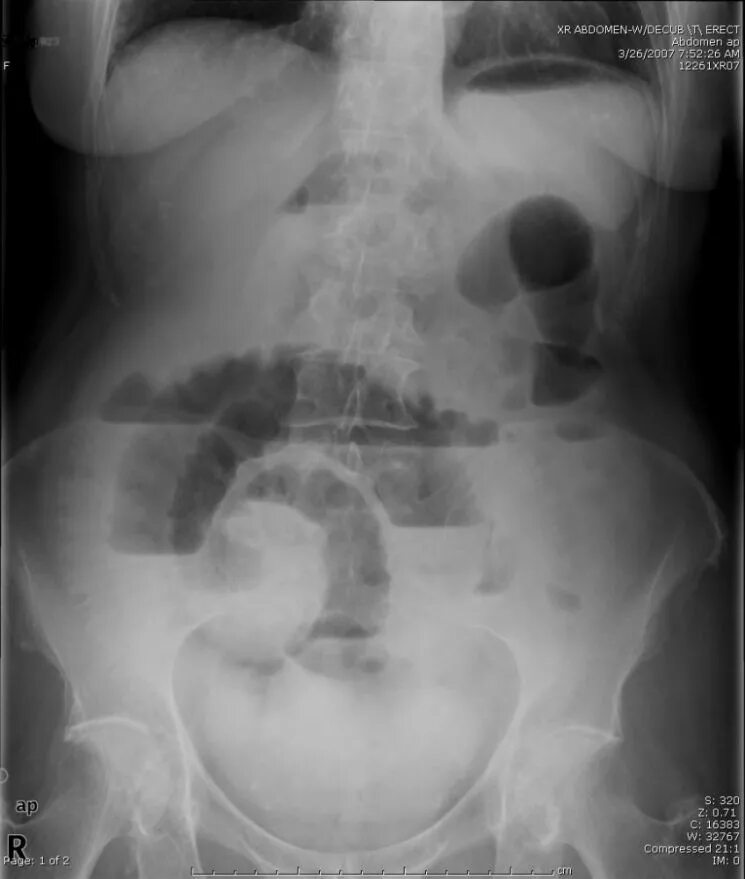

Симптом чаши